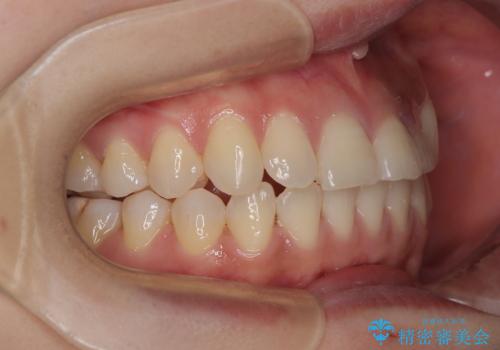

- 左上の前歯のがたつきを主訴に来院された患者様です。

上顎歯列が下顎の歯列に対して狭小であり、一部下顎の奥歯が上顎よりも外側に位置している状態でした。

上顎の歯列を拡大しスペースを設け、さらに左上の小臼歯を一本抜歯し左上の八重歯を歯列内に入れ整えていくことにしました。